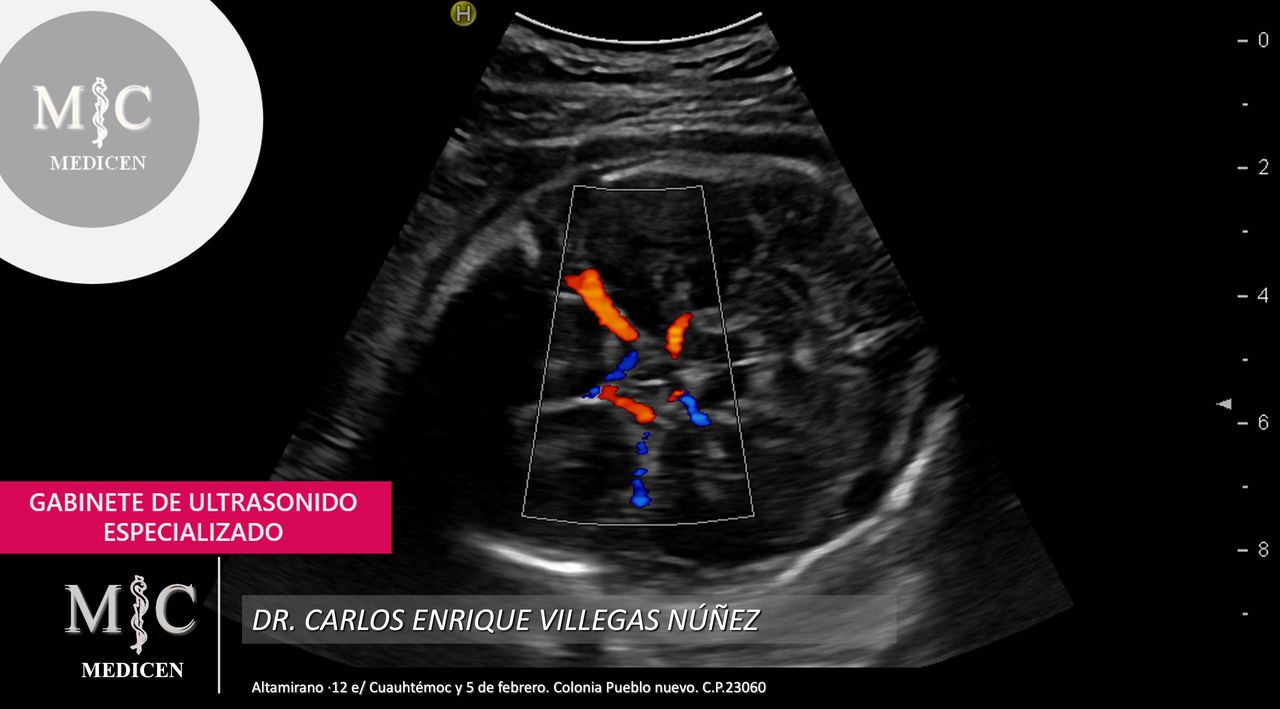

• Ultrasonido Doppler arterial en extremidades

• MEDICEN Ultrasonido 3D  •